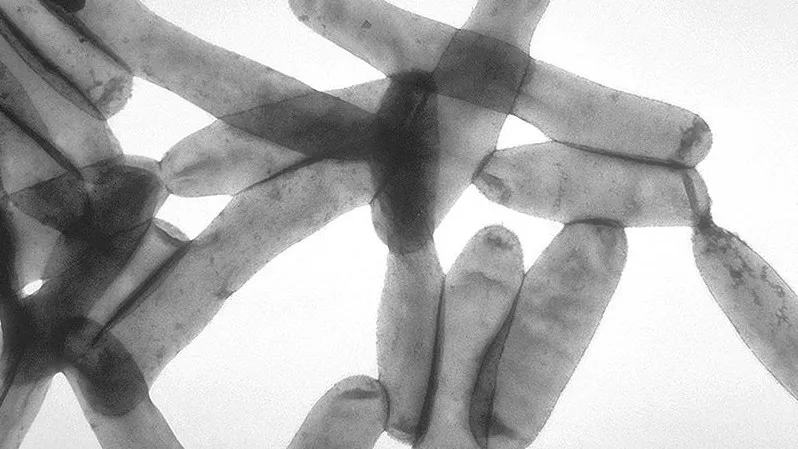

Zeker 753 Europese vakantieverblijven kampten tussen 1990 en 2011 met periodieke, soms jaarlijkse legionellabesmettingen. Dat schrijft NRC Handelsblad zaterdag op basis van eigen onderzoek. In totaal staan twaalfduizend adressen op de lijst die ooit eens in verband zijn gebracht met legionella, een bacterie die de dodelijke veteranenziekte kan veroorzaken.

Uit gegevens van Europese gezondheidsorganisaties blijkt dat er bij zeker 753 hotels, campings en appartementen gasten meerdere jaren de veteranenziekte opliepen. De namen van de accommodaties staan in een niet-publieke databank van de Europese gezondheidsorganisatie ECDC, onderdeel van de Europese Commissie.

Bij de accommodaties waar legionella vaak voorkomt is Italië koploper met 247 locaties. De bacterie zorgt onder toeristen in Europa jaarlijks voor tientallen doden en honderden zieken.